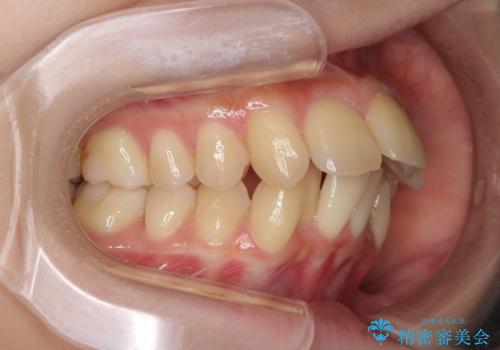

- 上下の出っ歯を気にして来院された患者様です。

口元を積極的に引っ込めるために、上下左右の小臼歯を4本抜歯することとしました。

右上前から2番目の歯が欠損しているため、①矯正治療により欠損部にスペースを作りインプラント補綴を行って前歯を左右対称に揃える、②左右非対称となるが、欠損補綴を行わずに排列する、のいずれかとなりますが、患者様と相談の上②にて矯正治療を行うこととしました。

変則的な歯列であったため、奥歯がしっかりと咬み合うのか、前歯はしっかりと排列できるのかと不安ではありましたが、結果としてはきれいに整った歯列にて終了することができました。